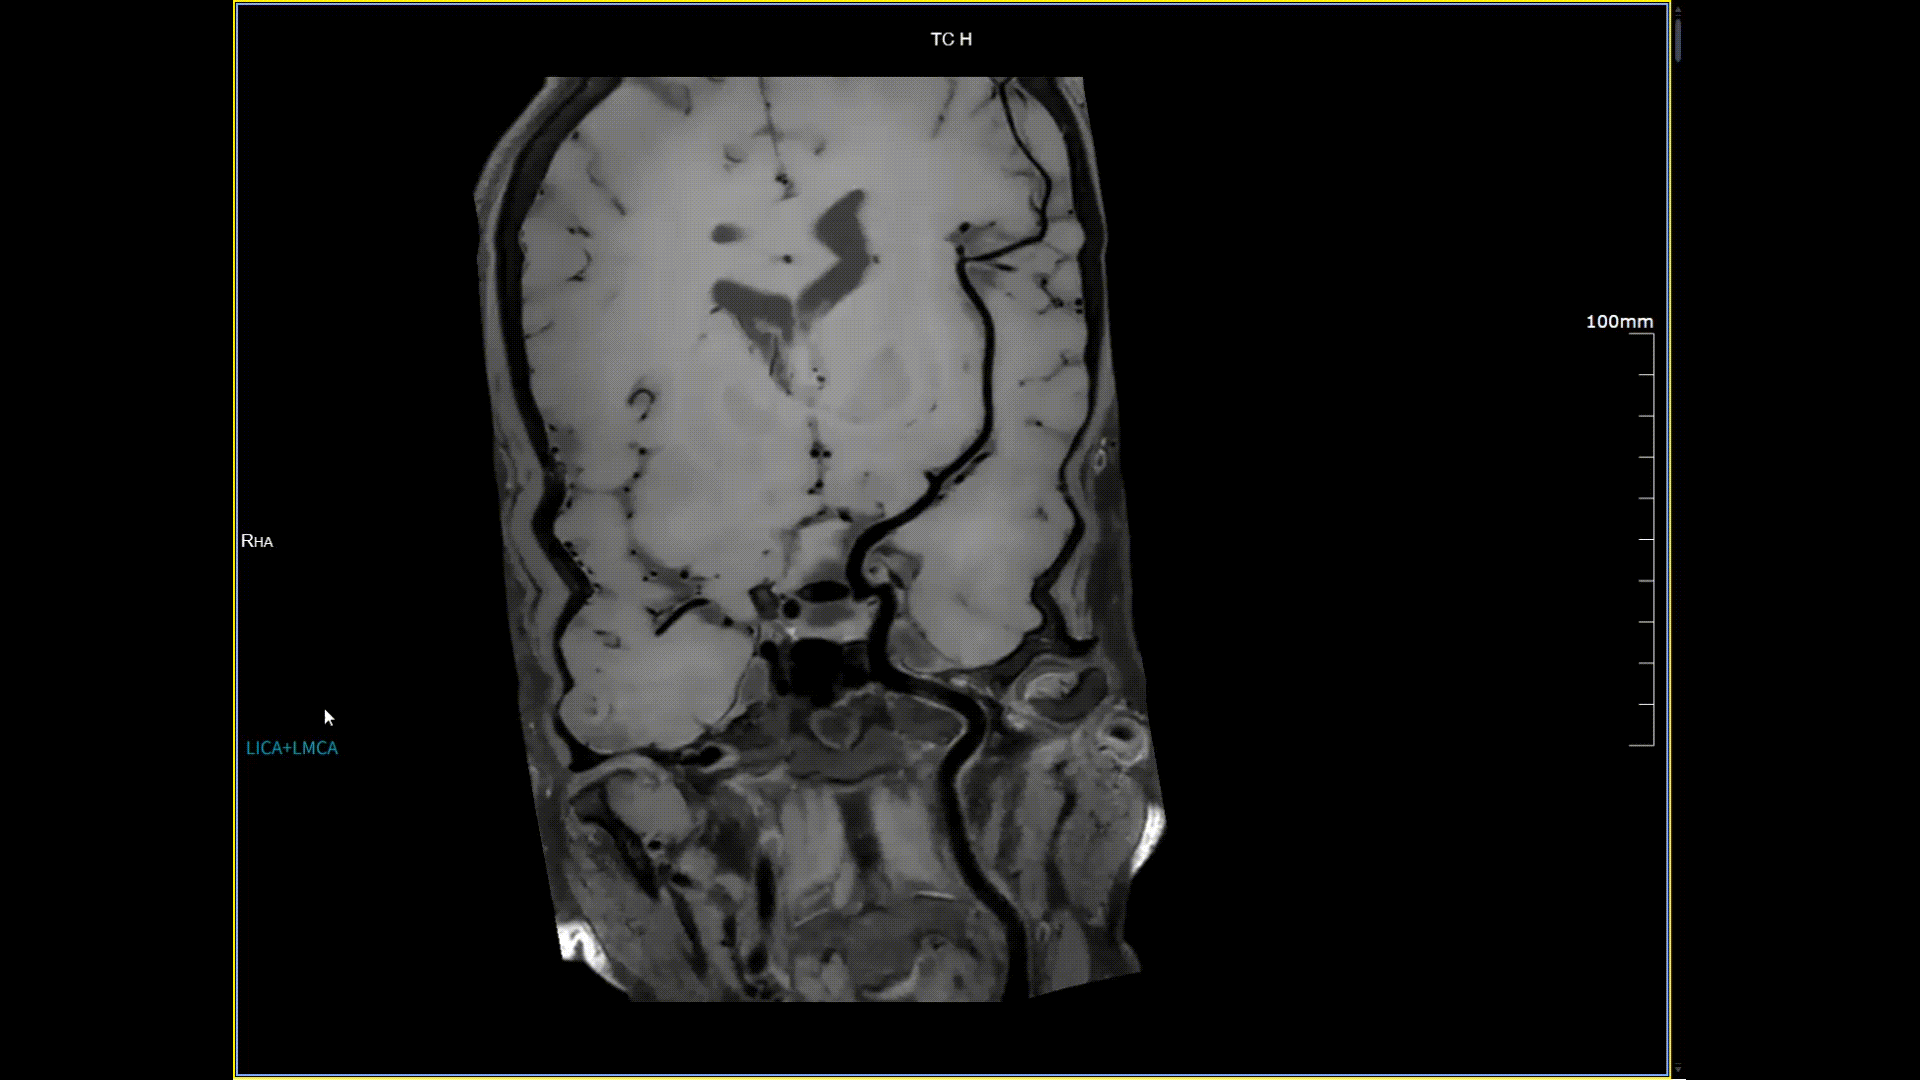

11月3日,一名30岁男性在我院接受了河北省首台5.0T超高场核磁共振头颅血管成像检查,图像清晰精准地反映出患者右侧小脑区域的血管畸形情况,该患者对我院的诊疗实力与服务温度给予充分肯定。相较于传统核磁共振,这台设备实现了“超高场全身各部位成像”的技术突破,它以业界领先的超高性能实现亚毫米级超高清成像,尤其在神经、心血管、体腹、关节等部位肿瘤疾病的早期发现、精准评估、个性化治疗方案制定中提供了的强大影像支持,将为全省乃至周边地区患者带来更优质、更精准的医疗服务。

5.0T磁场强度远高于其他设备,使得氢原子核在磁场中的响应信号极大地增强。这就像在安静的房间里能听清细微的声音一样,高信噪比能让医生看到更微小、更模糊的病变结构。例如上述患者的检查,该设备可以呈现0.2x0.2毫米高分辨率的图像以及动态显示血管走行,使得病变血管的细微解剖结构、分布及其与周边脑组织的关系得以直观呈现,为临床医生进行精准诊断并制定后续治疗方案提供了重要的影像学依据。

4D非造影剂头颅血管成像